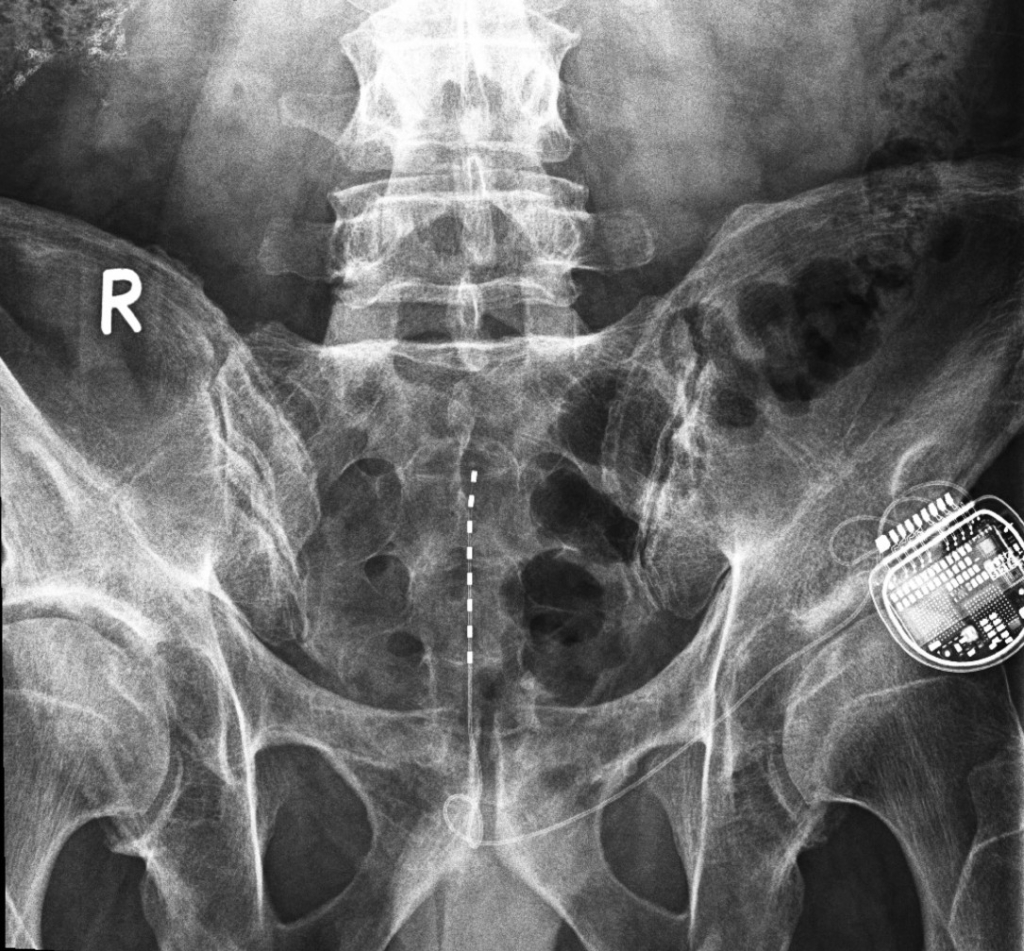

Bonus: the spinal cord stimulation

Jeroen talked about his experience with the spinal cord stimulation. In this procedure, an electrode (in th eshape of a needle) is placed internally near the spinal cord. Here it directly desrupts and in that way decreases the pain signals from the painful area to the brain through low frequency electrical currents, through a stimulator under the skin. This device can be charged through the skin and controlled by a remote control. It is more or less comparable with TENS which is external stimulation on the skin and through the peripheral nervous system. Spinal cord stimulation works internally and as the name indicates, directly on the central nervous system.

These are the pictures shared by Jeroen after his surgery. The dotted line is the electrode, the implanted device (stimulator) that sends the current is the round object.

This procedure only targets the pain, so it doesn’t solve the underlying problem itself and only works as long as the current is applied. On the other hand it is fully reversible by removing the device and has no side effects like you have with medication. Since it is minimal invasive surgery, there is hardly any tissue damage or scar tissue. It starts with a test period of 1 week, where only the electrode is inserted and the device remains external. After the trial period the patient and the surgeon evaluate and decide on a

permanent implant.